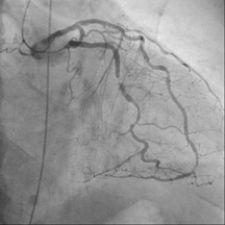

Designed with one 8-by-8-inch floor mounted cardiac C-arm and one 12- by-16-inch ceiling mounted C-arm, the Infinix DP-i/FD2 vascular X-ray system from Toshiba America Medical Systems enables physicians to obtain the high-quality images needed to perform both detailed peripheral vascular work and coronary studies without compromise for more efficient, comprehensive patient care. In addition, the system’s design allows clinicians to perform both coronary and vascular studies on the same table without moving the patient-saving time and increasing overall patient comfort.